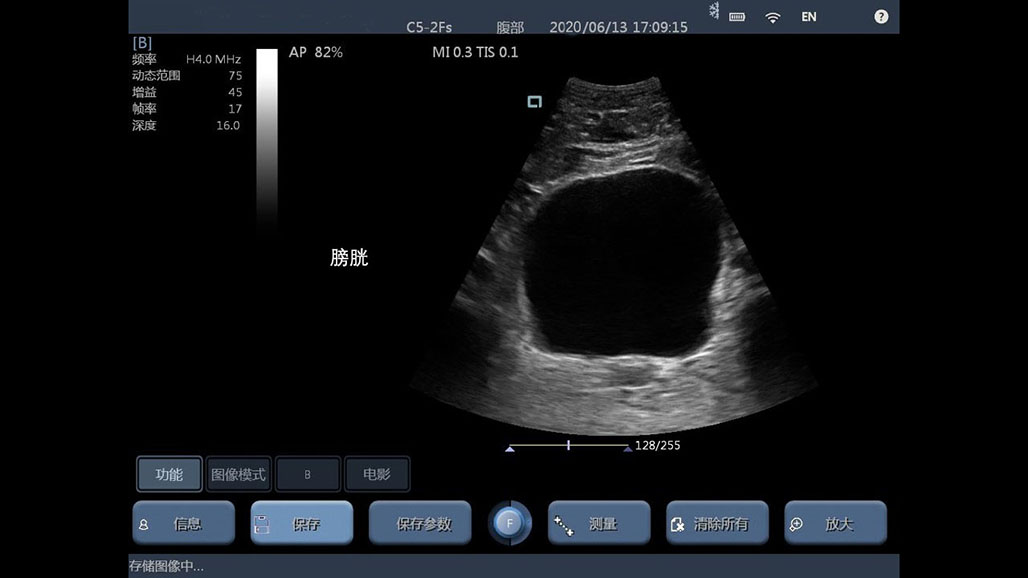

• 大凸

腹部

肾脏

妇科产科

心脏

肺等